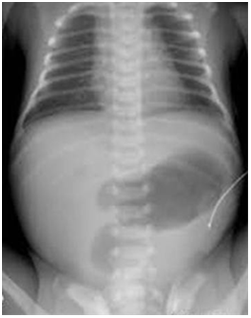

Histopathological diagnosis of colonic mucormycocis was a surprise and totally unsuspected. The excised large bowel wall demonstrated significant tissue infiltration by fungal organism. This fungal organism had irregular branching, nonseptated appearance and vascular invasion of intestinal blood vessel lumina by the fungal hyphae (Figure 2).

Figure 2 Histopathology slide showing colonic wall with significant infiltration by branching fungal hyphae. Also note colonic vascular invasion by the hyphae (H and E 40 ×).